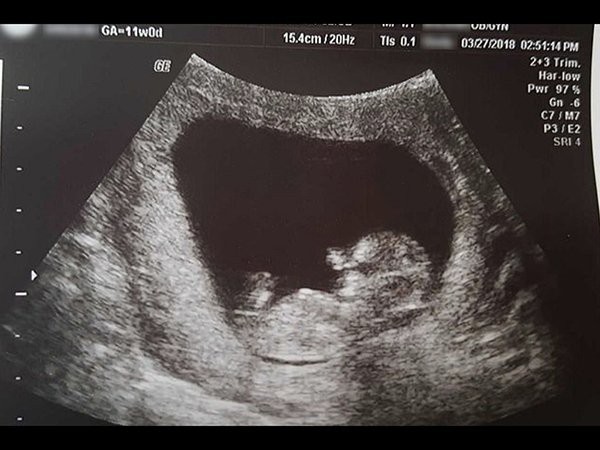

Old  Default Bức ảnh đau lòng về thai nhi 14 tuần tuổi được người mẹ dũng cảm chia sẻ

Một câu chuyện đã chạm đến trái tim của những người xem về những bức ảnh đau lòng của người mẹ mất đi một thai nhi 14 tuần tuổi, đã dũng cảm chia sẻ về những bức ảnh đau lòng này lên mạng.

Không có mất mát nào lớn hơn việc mất đi một đứa con. Một người phụ nữ Mỹ đã chia sẻ câu chuyện buồn của gia đình mình về việc mất đi thai nhi 14 tuần tuổi đồng thời chia sẻ những gì cô ấy cảm nhận về toàn bộ sự việc.

Bà mẹ cũng dũng cảm chia sẻ những bức ảnh đau lòng về thai nhi 14 tuần tuổi mà cô được bác sĩ yêu cầu phải phá bỏ. Toàn bộ ý tưởng về việc chia sẻ bức ảnh cho thấy thai nhi đã được hình thành hoàn toàn mặc dù nó chỉ dài 4 inch (tương đương hơn 10cm) và nặng 0,05 pound (tương đương 22,5g).

Christian cho biết, cô đã bị từ chối cơ hội chôn cất “đứa bé” đúng cách vì theo luật pháp Mỹ, “đứa bé” của cô không được công nhận là một đứa trẻ hợp pháp. Theo quy định ở Mỹ, thai nhi 20 tuần tuổi trở lên mới được công nhận là một đứa trẻ.

Christian Sharran không muốn "đứa bé" được xử lý như một chất thải y tế. Do đó, cô và chồng là anh Michael đã quyết định giữ “đứa bé” trong tủ lạnh trong vòng 1 tuần trước khi họ chôn cất “đứa bé” trong một hộp trồng cây chứa đầy hoa cẩm tú cầu trong vườn nhà. Và đây là những bức ảnh mà người mẹ này đã chia sẻ trên mạng.